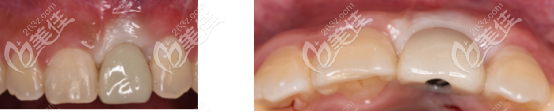

術后照片:

術后半年通過上面CT可以看出,骨量確實沒有發(fā)生吸收:

術后半年cbct照片中,可以看到牙齦愈合良好,而且骨量足夠做二期手術。

先安裝3.6×5mm愈合基臺,三周后進行印模的制取。

然后安裝臨時基臺+樹脂冠,用螺絲固位?;颊邔ρ拦诘念伾庑?,舒適度都比較滿意

總結:active種植體,不需要頻繁的更換鉆頭,所以在操作上就比較簡單,而且對牙齦的壓迫感小,穩(wěn)定性也優(yōu)于其他種植體。